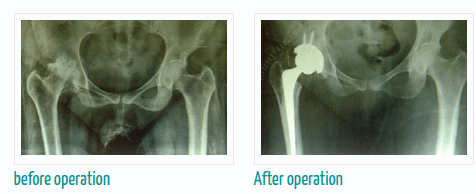

If you are thinking about getting arthroscopic surgery, consider seeing Dr. Murtaza Adeeb. He is a great doctor for joint replacement, and you can meet him at the Advanced Bone Care Clinic wanawadi Road Fatimanagar Pune.

Dr. Murtaza Adeeb is known for being really good at robotic knee, hip, and joint replacement surgery. To make an appointment with Dr. Murtaza Adeeb,